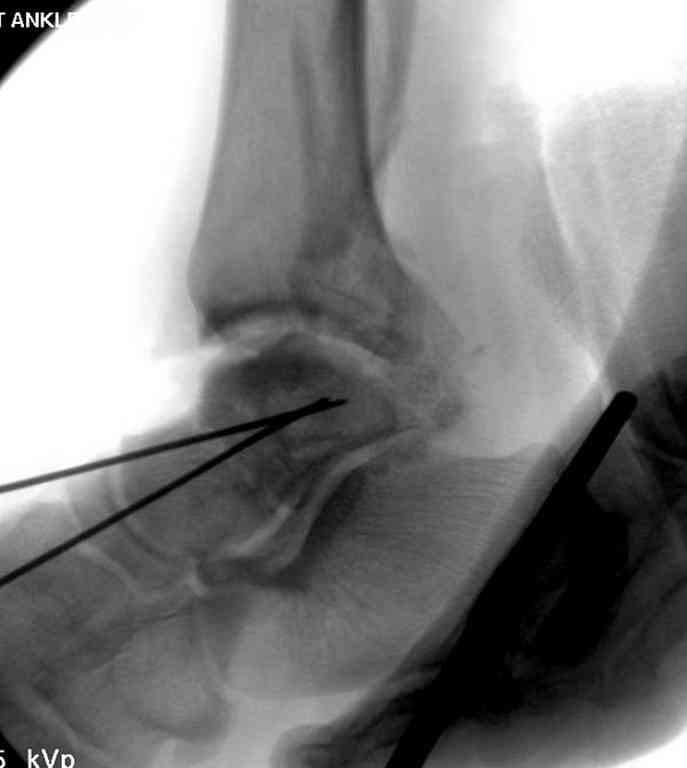

Второй случай прооперирован вчера.

10 дней назад поступил с открытым повреждением медиальной лодыжки и переломо вывихом таранной кости. Ургентно сделана репозиция с наложением наружного фиксатора + Irrigation&Debridment.

Во время репозиции выявили повреждение заднего сухожилия м. тибиалис и задней большеберцовой артерии. Медиальную рану удалось закрыть частично и установлен вакуум.

Дважды провели Irrigation&Debridment с заменой вакуума.

Вчера провели фиксацию.